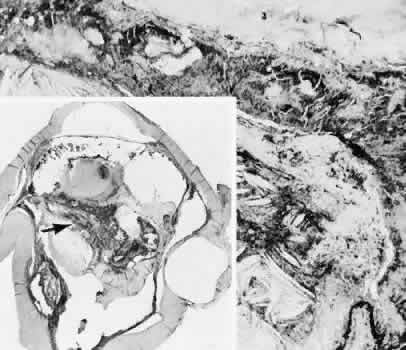

Many complications originate from so-called surgical confusion (Fig. 24). Most arise from a lack of knowledge, a lack of judgment, or problems in perception. At times, lack of attention to detail in preoperative planning may lead to a drug reaction, inadequate anesthesia, misplacement of incisions and sutures, or a patient who is unable to control a cough reflex. What is recognized histologically as the immediate cause of the problem may well have its origin in improper planning of the procedure.

Fig. 24. An unusual complication of cataract surgery. A. An unsuspected uveal mass was noted in the region of the pupil following cataract extraction. The mass was determined to be a metastatic carcinoma. The globe was enucleated. B. In a section of the enucleated globe, extensive tumor (T) can be identified though one hemisphere of the choroid, causing a secondary retinal detachment (RD). The detached retina is herniated through the cataract wound. (Hematoxylin-eosin stain; × 5.)